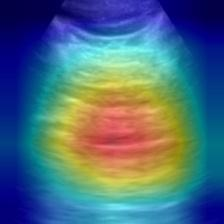

Most deep neural networks (DNNs) based ultrasound (US) medical image analysis models use pretrained backbones (e.g., ImageNet) for better model generalization. However, the domain gap between natural and medical images causes an inevitable performance bottleneck. To alleviate this problem, an US dataset named US-4 is constructed for direct pretraining on the same domain. It contains over 23,000 images from four US video sub-datasets. To learn robust features from US-4, we propose an US semi-supervised contrastive learning method, named USCL, for pretraining. In order to avoid high similarities between negative pairs as well as mine abundant visual features from limited US videos, USCL adopts a sample pair generation method to enrich the feature involved in a single step of contrastive optimization. Extensive experiments on several downstream tasks show the superiority of USCL pretraining against ImageNet pretraining and other state-of-the-art (SOTA) pretraining approaches. In particular, USCL pretrained backbone achieves fine-tuning accuracy of over 94% on POCUS dataset, which is 10% higher than 84% of the ImageNet pretrained model. The source codes of this work are available at https://github.com/983632847/USCL.